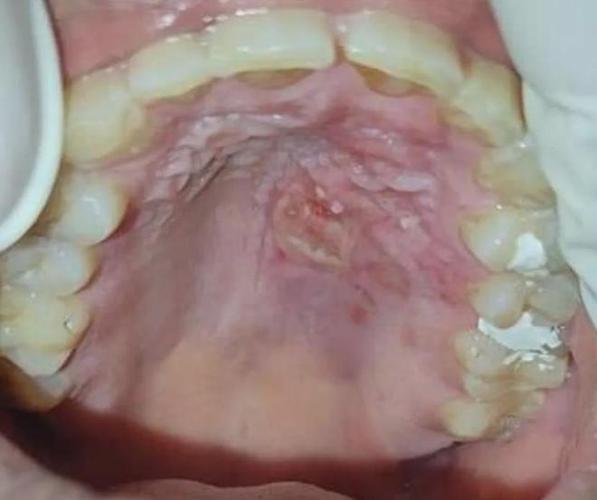

- 疱疹性口炎:由单纯疱疹病毒引起,初期可能是成簇的小水疱,很快会破溃,形成一片糜烂面或浅表溃疡,看起来就像“烂了一大块”,这种溃疡面积可能很广,除了牙龈、上颚,甚至可能出现在舌头和嘴唇上,并可能伴有发烧、淋巴结肿大等全身症状。